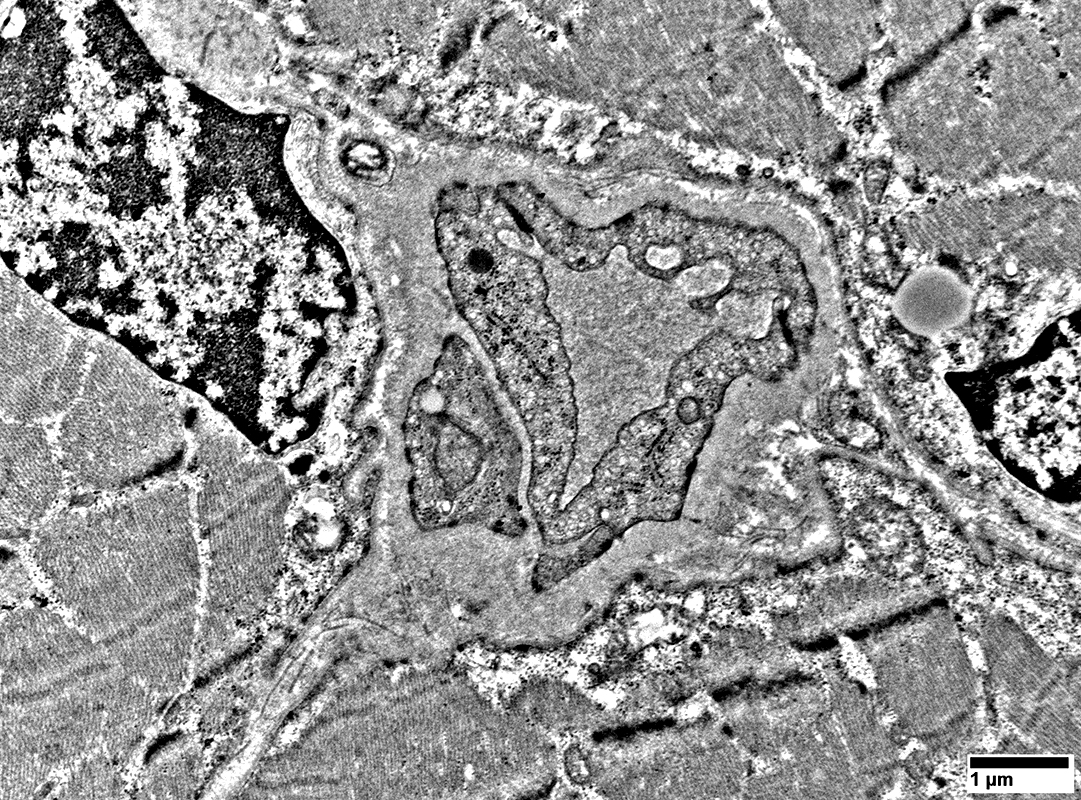

MELAS: Mitochondrial Ultrastructure

From: R Schmidt

Pericytes   Mitochondrial proliferation & enlargement (Black arrows)

Endothelial cells   Multiple small vacuoles (White arrows)

Large cells near vessels with

Mitochondrial proliferation & enlargement

Lipid droplets

Large cells near vessels with cytoplasm nearly replaced by